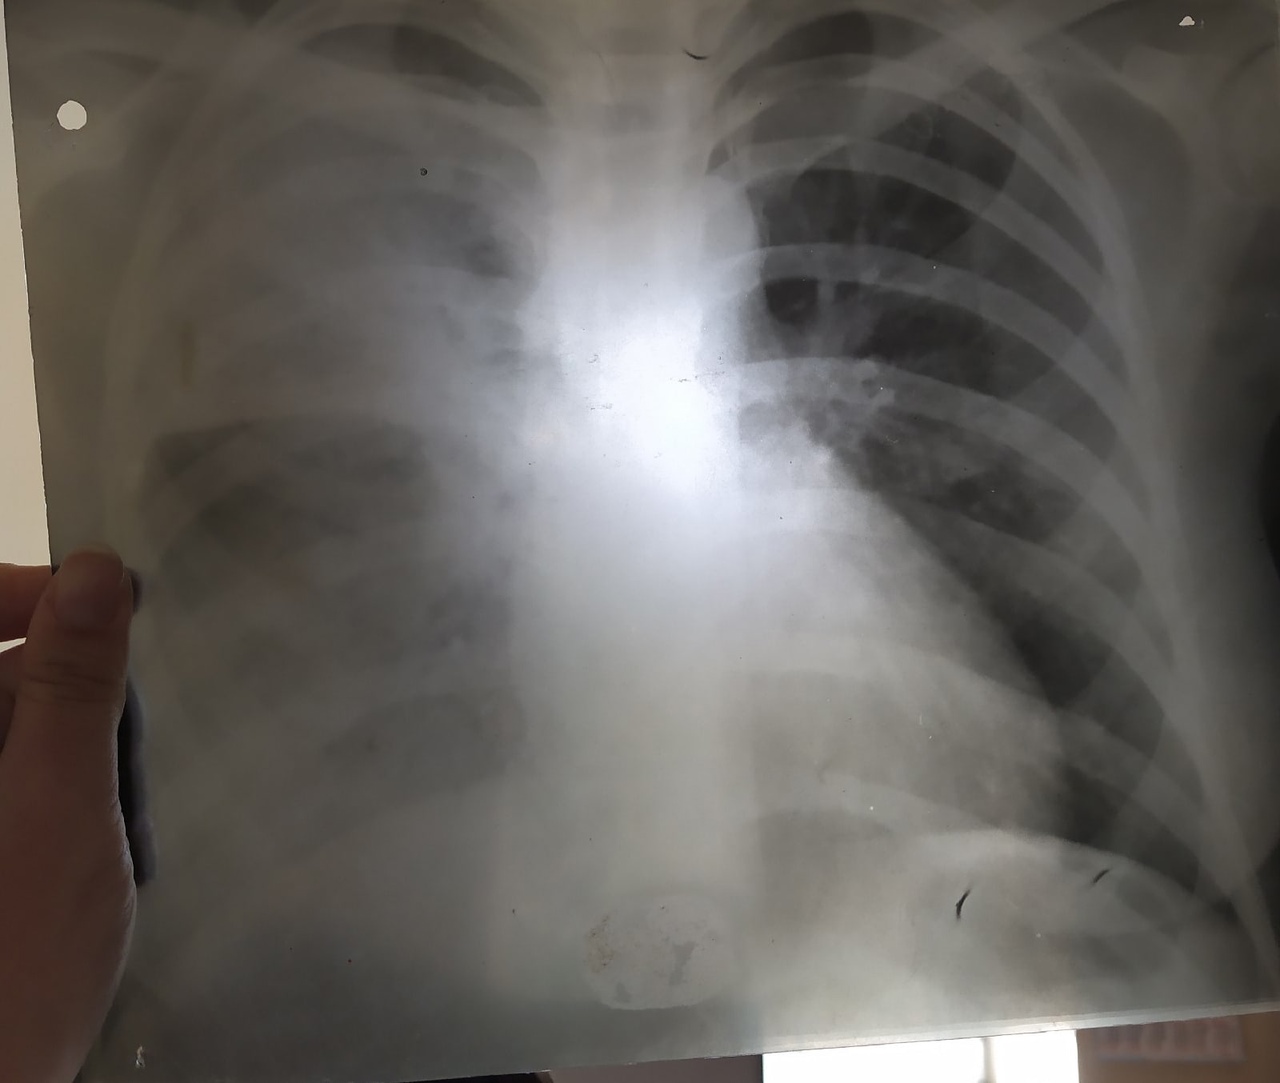

Здравствуйте, помогите, пожалуйста с описанием. Какая имеет место быть форма туберкулеза?

Тип: Клиническое наблюдение

Область: Грудная клетка и верхние дыхательные пути, Средостение и сердце

Модальность: Rg

Дата: 18.05.2022 - 16:28